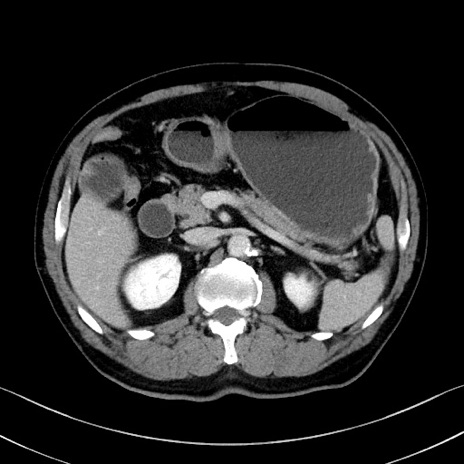

症例35(横断像)

冠状断像

【症例】70歳代 男性

【主訴】腹部膨満、嘔吐

【現病歴】昨日より腹部膨満感出現。本日増悪し、仙痛出現。嘔吐あり、受診。

【既往歴】糖尿病、胆摘後

【身体所見】BP 149/80mmHg、HR 74/min、BT 35.9℃、腹部:膨満、軟、圧痛なし。腸雑音減弱あり。上腹部正中切開瘢痕あり。

【データ】WBC 13500、CRP 1.72